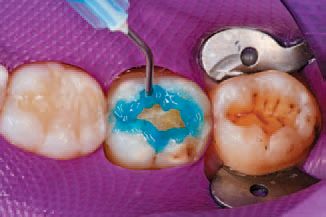

Preparation then began on tooth No. 31. Ivoclar Vivadent’s Total Etch was applied to the enamel and allowed to penetrate for 15 seconds, after which the etchant was applied to the dentin and allowed to penetrate for 10 seconds to ensure proper etching of both surfaces (Figs. 14 and 15). The etchant was then rinsed off with water, and all excess moisture was removed.